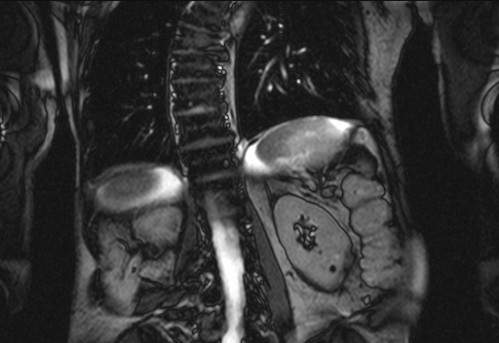

Auffälliges Abdomen bei der Vorsorgeuntersuchung einer älteren Dame

ICD: C64

68 Jahre alte Frau. Sie geht zur Darmspiegelung im Rahmen ihrer Krebsvorsorgeuntersuchung. Der Internist bemerkt bei der ergänzenden sonografischen Untersuchung des Abdomens einen auffälligen Befund.